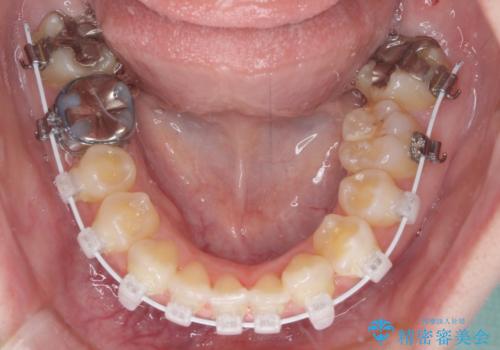

- 矯正装置

- 審美装置

- 左上の八重歯と前歯のデコボコを気にして来院された患者様です。

下顎が左側にズレており、下顎前歯は1歯欠損していたため、左上小臼歯1本を抜歯し、ワイヤー装置にて矯正治療を行うこととしました。

骨格のズレと歯の欠損があったため、仕上がりの調整に時間がかかると思いましたが、舌突出癖の改善や顎間ゴムの装着をしっかりと行ってくださったので、速やかに治療を終えることができました。